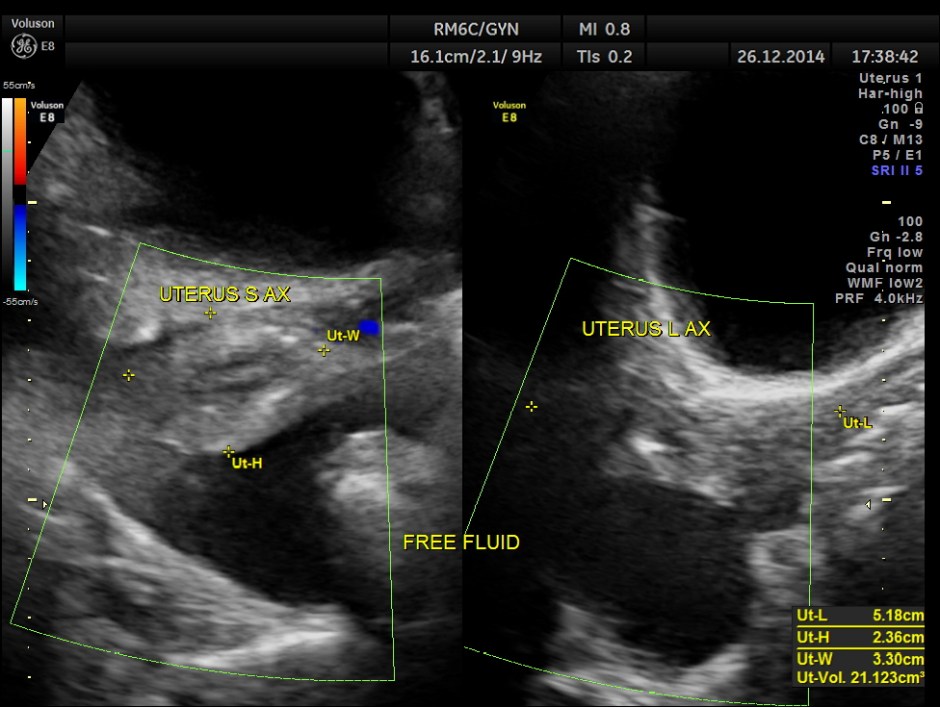

free fluid seen in the abdomen and pelvis , suggestive of possible peritoneal spread of Ca.